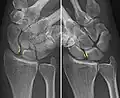

Static scapholunate dissociation

Dynamic instability: Increased scapholunate distance (between yellow lines) upon ulnar deviation of the wrist, but not otherwise.